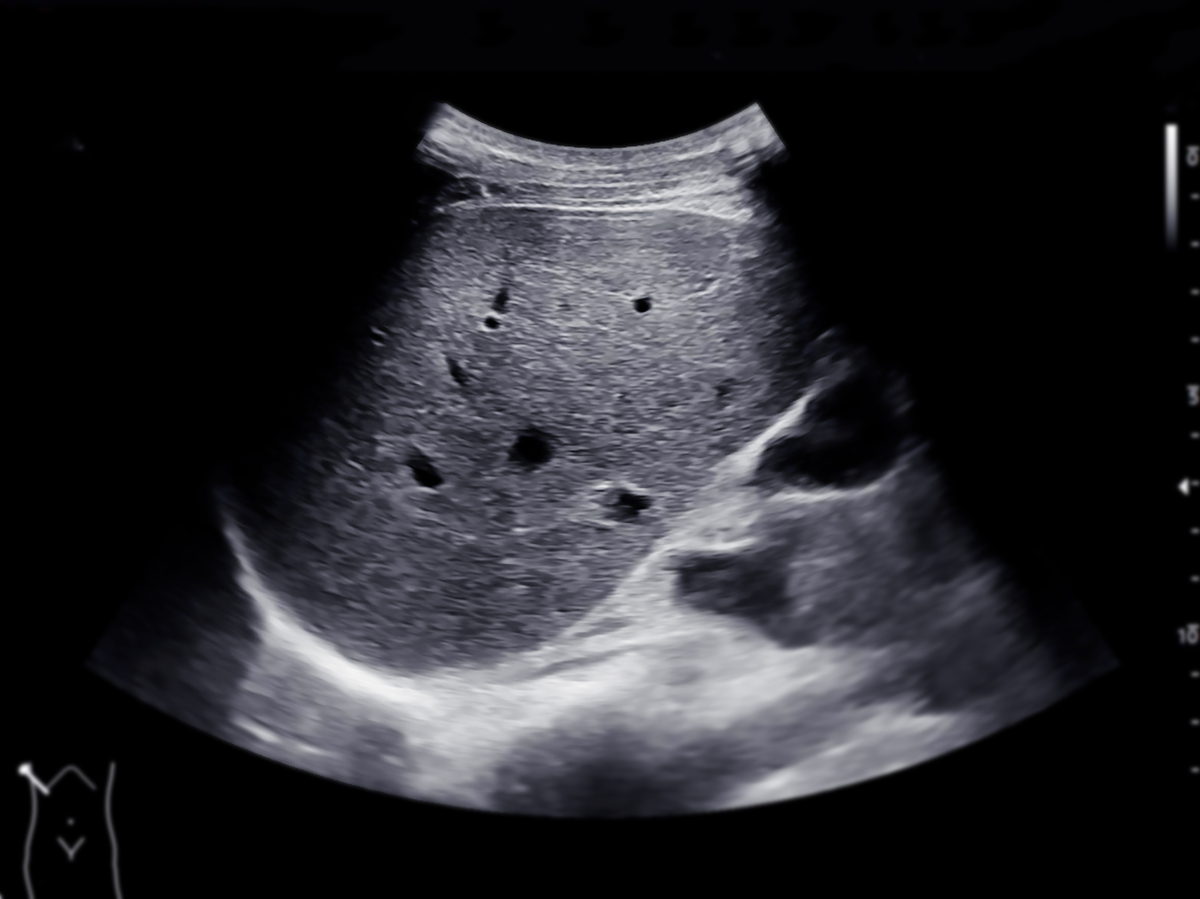

超声检查腋窝淋巴结时,可以按照以下方式分区:

在分区时,需要根据患者的体位和超声探头的位置,结合解剖学知识进行判断和定位。同时,需要注意各个区域的淋巴结大小、形态、边缘、内部回声等特征,以及与周围组织的关系,对淋巴结的异常进行评估和诊断。